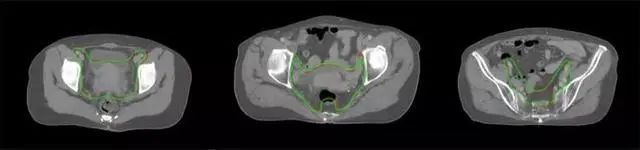

技術(shù)原理

基于深度學(xué)習(xí)人工智能的放療靶區(qū)智能勾畫技術(shù)和自動計劃技術(shù),基于全面的市場調(diào)研和臨床專業(yè)意見,采用獨創(chuàng)的基于小樣本量的人工智能算法,實現(xiàn)放療靶區(qū)和危及器官的快速全自動勾畫。

產(chǎn)品優(yōu)勢

縮短至幾分鐘內(nèi)便可完成,大幅提升了放療效率,且人工智能平臺完成的靶區(qū)勾畫可基本滿足臨床醫(yī)生需求,專家只需審核時細(xì)微調(diào)整,可顯著提高靶區(qū)勾畫的規(guī)范化及精準(zhǔn)度,讓放療智能化,標(biāo)準(zhǔn)化。可覆蓋食管癌、鼻咽癌、直腸癌、宮頸癌、肺癌等多種病種。